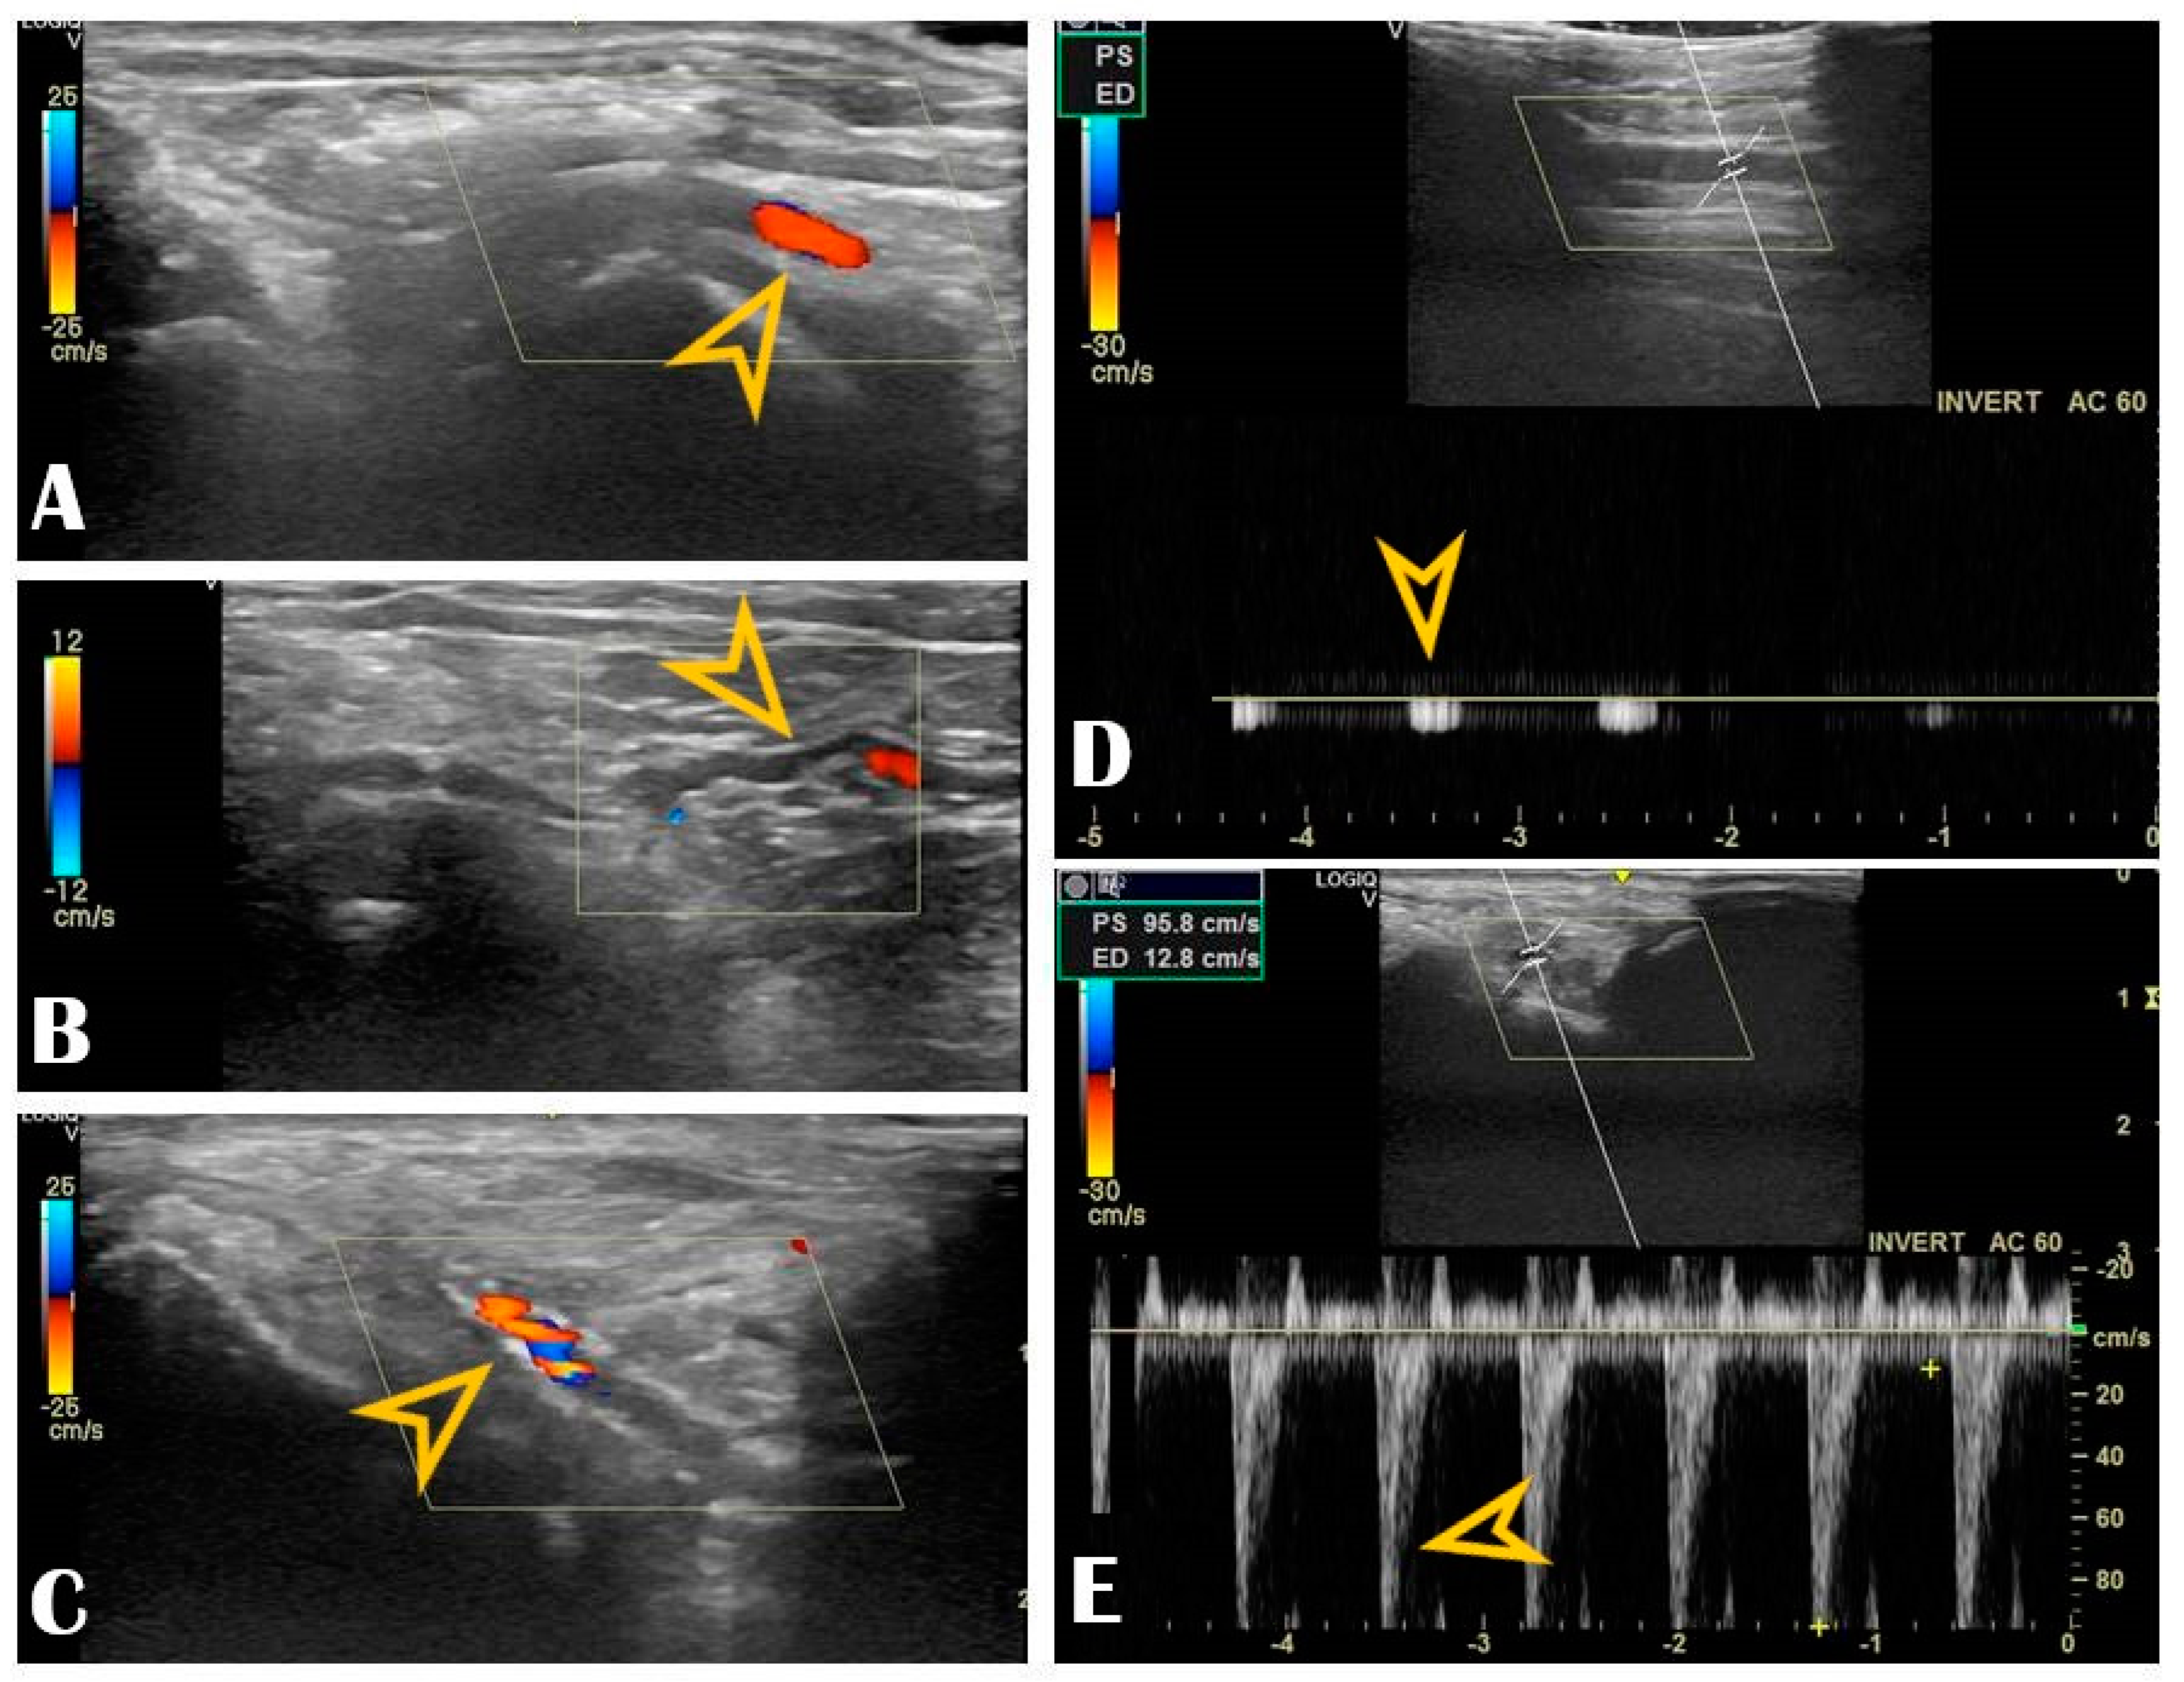

The key anatomical structures that should be identified in the anatomical snuffbox are illustrated in Figure 2. The radial artery should be scanned along the snuffbox in the short-axis view and then switched to the long-axis view in order to select the best site for puncture, aiming for sufficient caliber (ideally > 1.8 mm) and the absence of tortuosity and disease. The common long-axis view is exemplified in Figure 3 along with other pathological variants of reduced or increased peak systolic velocities. The puncture area (the triangle) is separated in two by the tendon of the extensor pollicis longus muscle, which is prominent and easily palpable, and which impels the operator to puncture distal or proximal to it. The true snuffbox area is proximal to the tendon of the extensor pollicis longus muscle, as illustrated in Figure 1 (blue arrow) and Figure 2 where the artery is located laterally to the tendon. The artery then continues under the tendon, actually entering the first intermetacarpal space where it can be palpated and punctured again (dorsum of the hand area—not so preferred among operators, Figure 1, yellow arrow), and finally, it continues its course medially and deeply, forming anastomoses with the ulnar artery. The skin is then punctured parallel to the probe in the exact center of the probe.

Figure 3. Radial vascular ultrasound findings: Panel (A): Normal radial artery (arrow). Panel (B): Radial artery tortuosity (arrow). Panel (C): Radial artery calcification (arrow). Panel (D): Occluded radial artery (the arrow shows the monophasic curve and the decreased peak systolic velocity). Panel (E): Radial artery stenosis (the arrow shows the increased peak systolic velocity).

Our center experience reached 1240 consecutive patients who underwent DRA between 2019–2021, all of them under US guidance (from which, 75% of patients received coronary angiography and/or intervention, and the remaining 25% received various peripheral interventions). The extensive results of the registry were published in a multicenter study [4]. DRA was successfully punctured in 97% of all patients, always with ultrasound guidance, with puncture and sheath insertion up to two attempts in the vast majority of patients [4]. We encountered only 2.58% access site crossovers (successful arterial puncture but failed sheath insertion), mainly performed via the ipsilateral conventional PRA, allowing the initial vascular access strategy to be carried out and waiving transfemoral access [4]. Factors leading to crossover were RAO, small vessel diameter, tortuosity, or significant atherosclerosis. The remarkably low crossover rate was due to the pre-procedural US screening that deferred small distal radial arteries. The indication spectrum was broad, from coronary interventions to structural or peripheral. The maximum sheath size inserted was 9F, for transradial balloon aortic valvuloplasty [24]. No major ischemic or bleeding complications were recorded. We have learned along the way that US is useful beyond guiding the puncture. Scanning the artery before the puncture can provide details about the condition of the artery. Findings worthy of mentioning are that multiple attempts lead to needle-induced microhematomas between the intima and media that subsequently narrow or occlude the vessel (by extrinsic compression), giving the operator’s impression that the vessel became “spastic” (Figure 6, panel B). Another peculiar finding observed by our operators during RUS was needle-induced fluid turbulence when penetrating the artery, a highly specific sign of successful puncture (Supplementary Materials Video S1). Plaque formation, calcinosis, reduced lumen, or occlusion are accessible for diagnosis (Figure 6, panel C). A recent study found a significant correlation between radial calcification and coronary calcification; therefore, US may even play a key role in predicting severe coronary artery disease [25]. Moreover, the multivariable logistic regression found a strong correlation between risk factors such as age, smoking, chronic kidney disease, and diabetes mellitus and radial artery calcification [25]. This helps to understand how metabolic systemic diseases affect even the far end of the arterial tree [26,27]. This is of increased importance when the radial artery is potentially considered as a coronary bypass conduit, and the quality of the vessel must be carefully evaluated with US.